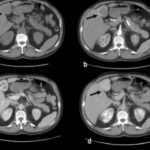

La hiperplasia nodular focal es el segundo tumor benigno más frecuente después del hemangioma. Tiene mayor incidencia en mujeres jóvenes. Histológicamente es un tumor hiperplásico que conserva los mismos componentes del tejido hepático normal, pero con una arquitectura alterada (hepatocitos normales + células de Kupffer + conductos biliares primitivos no conectados con la vía biliar normal). Presentan una cicatriz central de tejido fibroso con estructuras vasculares dilatadas y ectásicas. En la tomografía multicorte sin contraste intravenoso se evidencia como una lesión homogénea bien definida, hipo o isodensa con respecto al parénquima hepático. En la tomografía multicorte multifásica, después de la administración del medio de contraste, tiene un comportamiento típico.

- Fase arterial: reforzamiento intenso.

- Fase portal: es isodenso o ligeramente hiperdenso con respecto al parénquima.

- Fase tardía: lesión totalmente isodensa, no se visualiza, excepto porque puede producir efecto de masa sobre el parénquima adyacente.

La cicatriz central (Anexos 21 y 22), al estar menos vascularizada, no refuerza en fase arterial. Sin embargo, en fase tardía muestra hiperdensidad cuando ya el resto de la lesión se ha hecho isodensa.(18)